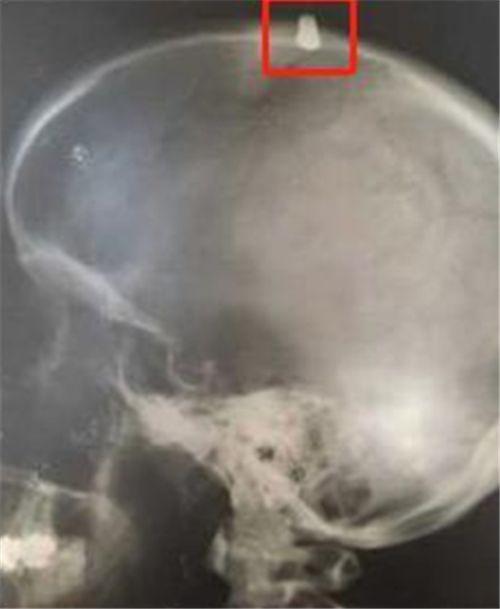

但琳达看他的样子不对劲,带着他上了医院,没想一颗0.22口径的*弹子**打在了头骨盖最厚的地方,但由于*弹子**较小,冲击力不大,被骨头卡住了,丹尼斯才能活下来,虽然警方立刻介入,但由于周边没有任何监控,也没有目击者,此事也就暂停调查了。